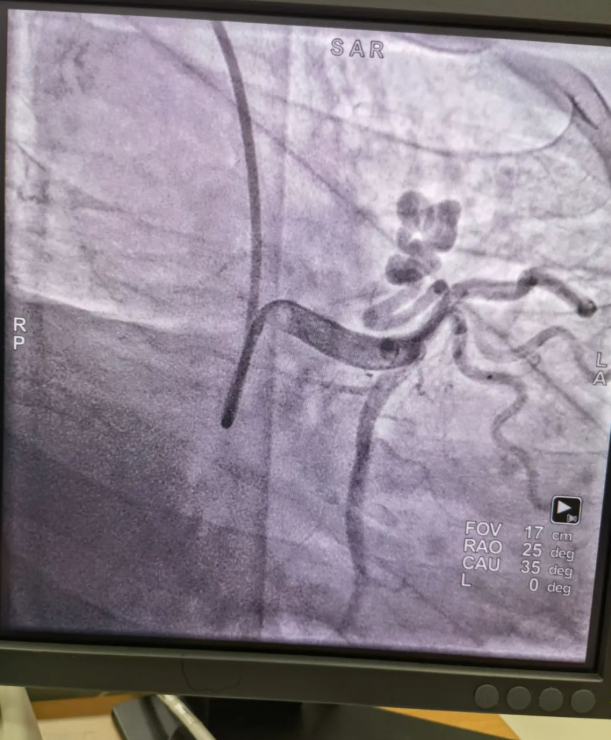

不久前,來(lái)自新疆的患者石先生去年至今反復(fù)胸悶、氣短、胸痛,就診于新疆某院,懷疑“冠心病”,住院行冠狀動(dòng)脈造影術(shù),石先生造影提示“冠狀動(dòng)脈肺動(dòng)脈瘺”,而他并非“冠心病”,所以給予的“冠心病”治療,效果不佳。出院后仍反復(fù)出現(xiàn)胸痛、胸悶、氣短等癥狀,經(jīng)親友介紹了解到西安國(guó)際醫(yī)學(xué)中心醫(yī)院心臟病醫(yī)院心臟內(nèi)科二病區(qū)曾廣偉主任,多年來(lái)潛心研究心臟病介入治療,成功主刀救治了許許多多高危復(fù)雜病例,尤其是在先心病及結(jié)構(gòu)性心臟病封堵,以及冠心病、心律失常射頻消融及起搏治療等方面積累了豐富的診療經(jīng)驗(yàn)。

此病例罕見(jiàn),在曾廣偉從醫(yī)18年生涯里曾碰到有2個(gè)印象深刻的病例,患者分別是53歲和66歲,當(dāng)時(shí)建議患者入院進(jìn)行動(dòng)脈瘺的封堵術(shù),但患者和家屬考慮到這個(gè)手術(shù)案例極少,風(fēng)險(xiǎn)也高,均未接受手術(shù)治療建議,只是能采取藥物保守治療,出院后隨訪得知患者癥狀緩解效果不佳,后來(lái)在隨訪中也與53歲患者失去了聯(lián)系,而66歲患者因冠狀動(dòng)脈肺動(dòng)脈瘺出現(xiàn)反復(fù)心衰,在當(dāng)?shù)蒯t(yī)院藥物治療,短短2年時(shí)間,患者因?yàn)閯?dòng)脈瘺未及時(shí)手術(shù)失去了生命。所以此次患者石先生到訪,曾廣偉主任在詳細(xì)掌握病例資料基礎(chǔ)上,果斷建議進(jìn)行動(dòng)脈瘺的封堵術(shù)治療,為了提高手術(shù)成功率和精準(zhǔn)度,曾廣偉主任搜集相關(guān)診療資料,反復(fù)推演論證,經(jīng)過(guò)相當(dāng)充足的準(zhǔn)備工作,于5月18日成功進(jìn)行了封堵手術(shù),完全堵上了瘺口。

患者術(shù)后第2天,已經(jīng)沒(méi)有明顯的胸悶、氣短、胸痛等癥狀,目前身體狀態(tài)良好。本次手術(shù)曾廣偉主任及其團(tuán)隊(duì),采取從右手臂一根血管進(jìn)入,并在2小時(shí)之內(nèi)完美封堵,創(chuàng)口小,痛苦小。手術(shù)雖然難度大、風(fēng)險(xiǎn)高,相關(guān)案例也少,但是曾廣偉主任主刀即在巔峰,這樣一臺(tái)完美的手術(shù)靠的不是運(yùn)氣,是豐富的臨床手術(shù)經(jīng)驗(yàn),扎實(shí)的專業(yè)知識(shí)儲(chǔ)備,以及對(duì)醫(yī)療事業(yè)的孜孜追求。

冠狀動(dòng)脈瘺是指冠狀動(dòng)脈與心腔、冠狀靜脈、肺動(dòng)脈等的異常連接,是一種少見(jiàn)的先天性心臟病,發(fā)病率為1.3%。而冠狀動(dòng)脈肺動(dòng)脈瘺是冠狀動(dòng)脈與肺動(dòng)脈之間產(chǎn)生的一種血管性瘺口,導(dǎo)致冠狀動(dòng)脈里的血液流入肺動(dòng)脈里,使冠狀動(dòng)脈里血液流量減少,出現(xiàn)心肌供血不足,冠狀動(dòng)脈肺動(dòng)脈瘺會(huì)使患者出現(xiàn)胸部疼痛、胸悶、呼吸困難、頭暈、乏力等一系列癥狀,隨著疾病不斷進(jìn)展,可引發(fā)心功能的障礙和心肌缺血,肺動(dòng)脈會(huì)逐漸形成肺動(dòng)脈高壓,還可能導(dǎo)致動(dòng)脈瘤的破裂,甚至威脅病人的生命安全,所以早期發(fā)現(xiàn)和治療冠狀動(dòng)脈肺動(dòng)脈瘺,對(duì)病人的預(yù)后改善具有重要的意義。